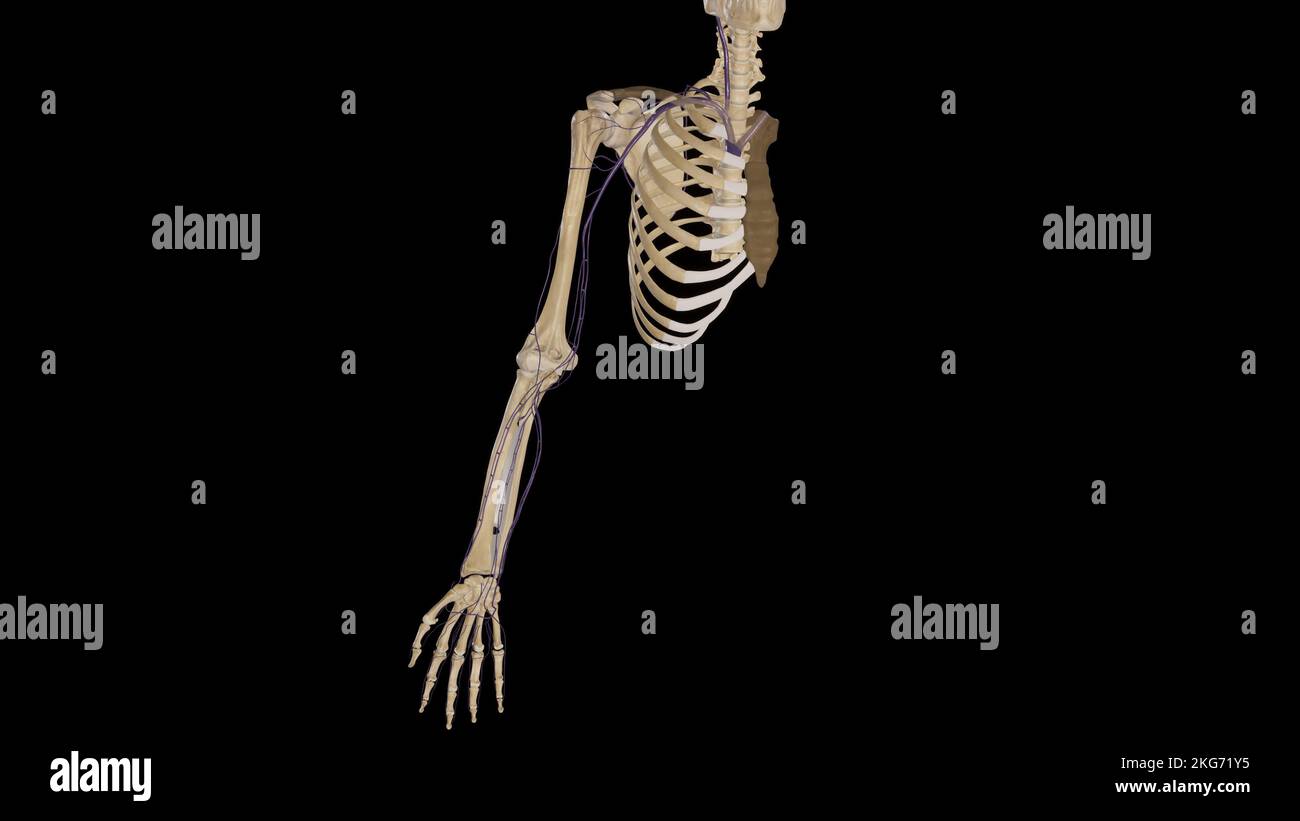

RMJE7CWP–Der Plexus brachialis ist ein Nervennetz im Nacken- und Schulterbereich, das für die motorischen und sensorischen Funktionen der oberen Extremität von wesentlicher Bedeutung ist. Das Bild zeigt den Plexus brachialis an seiner anatomischen Position.